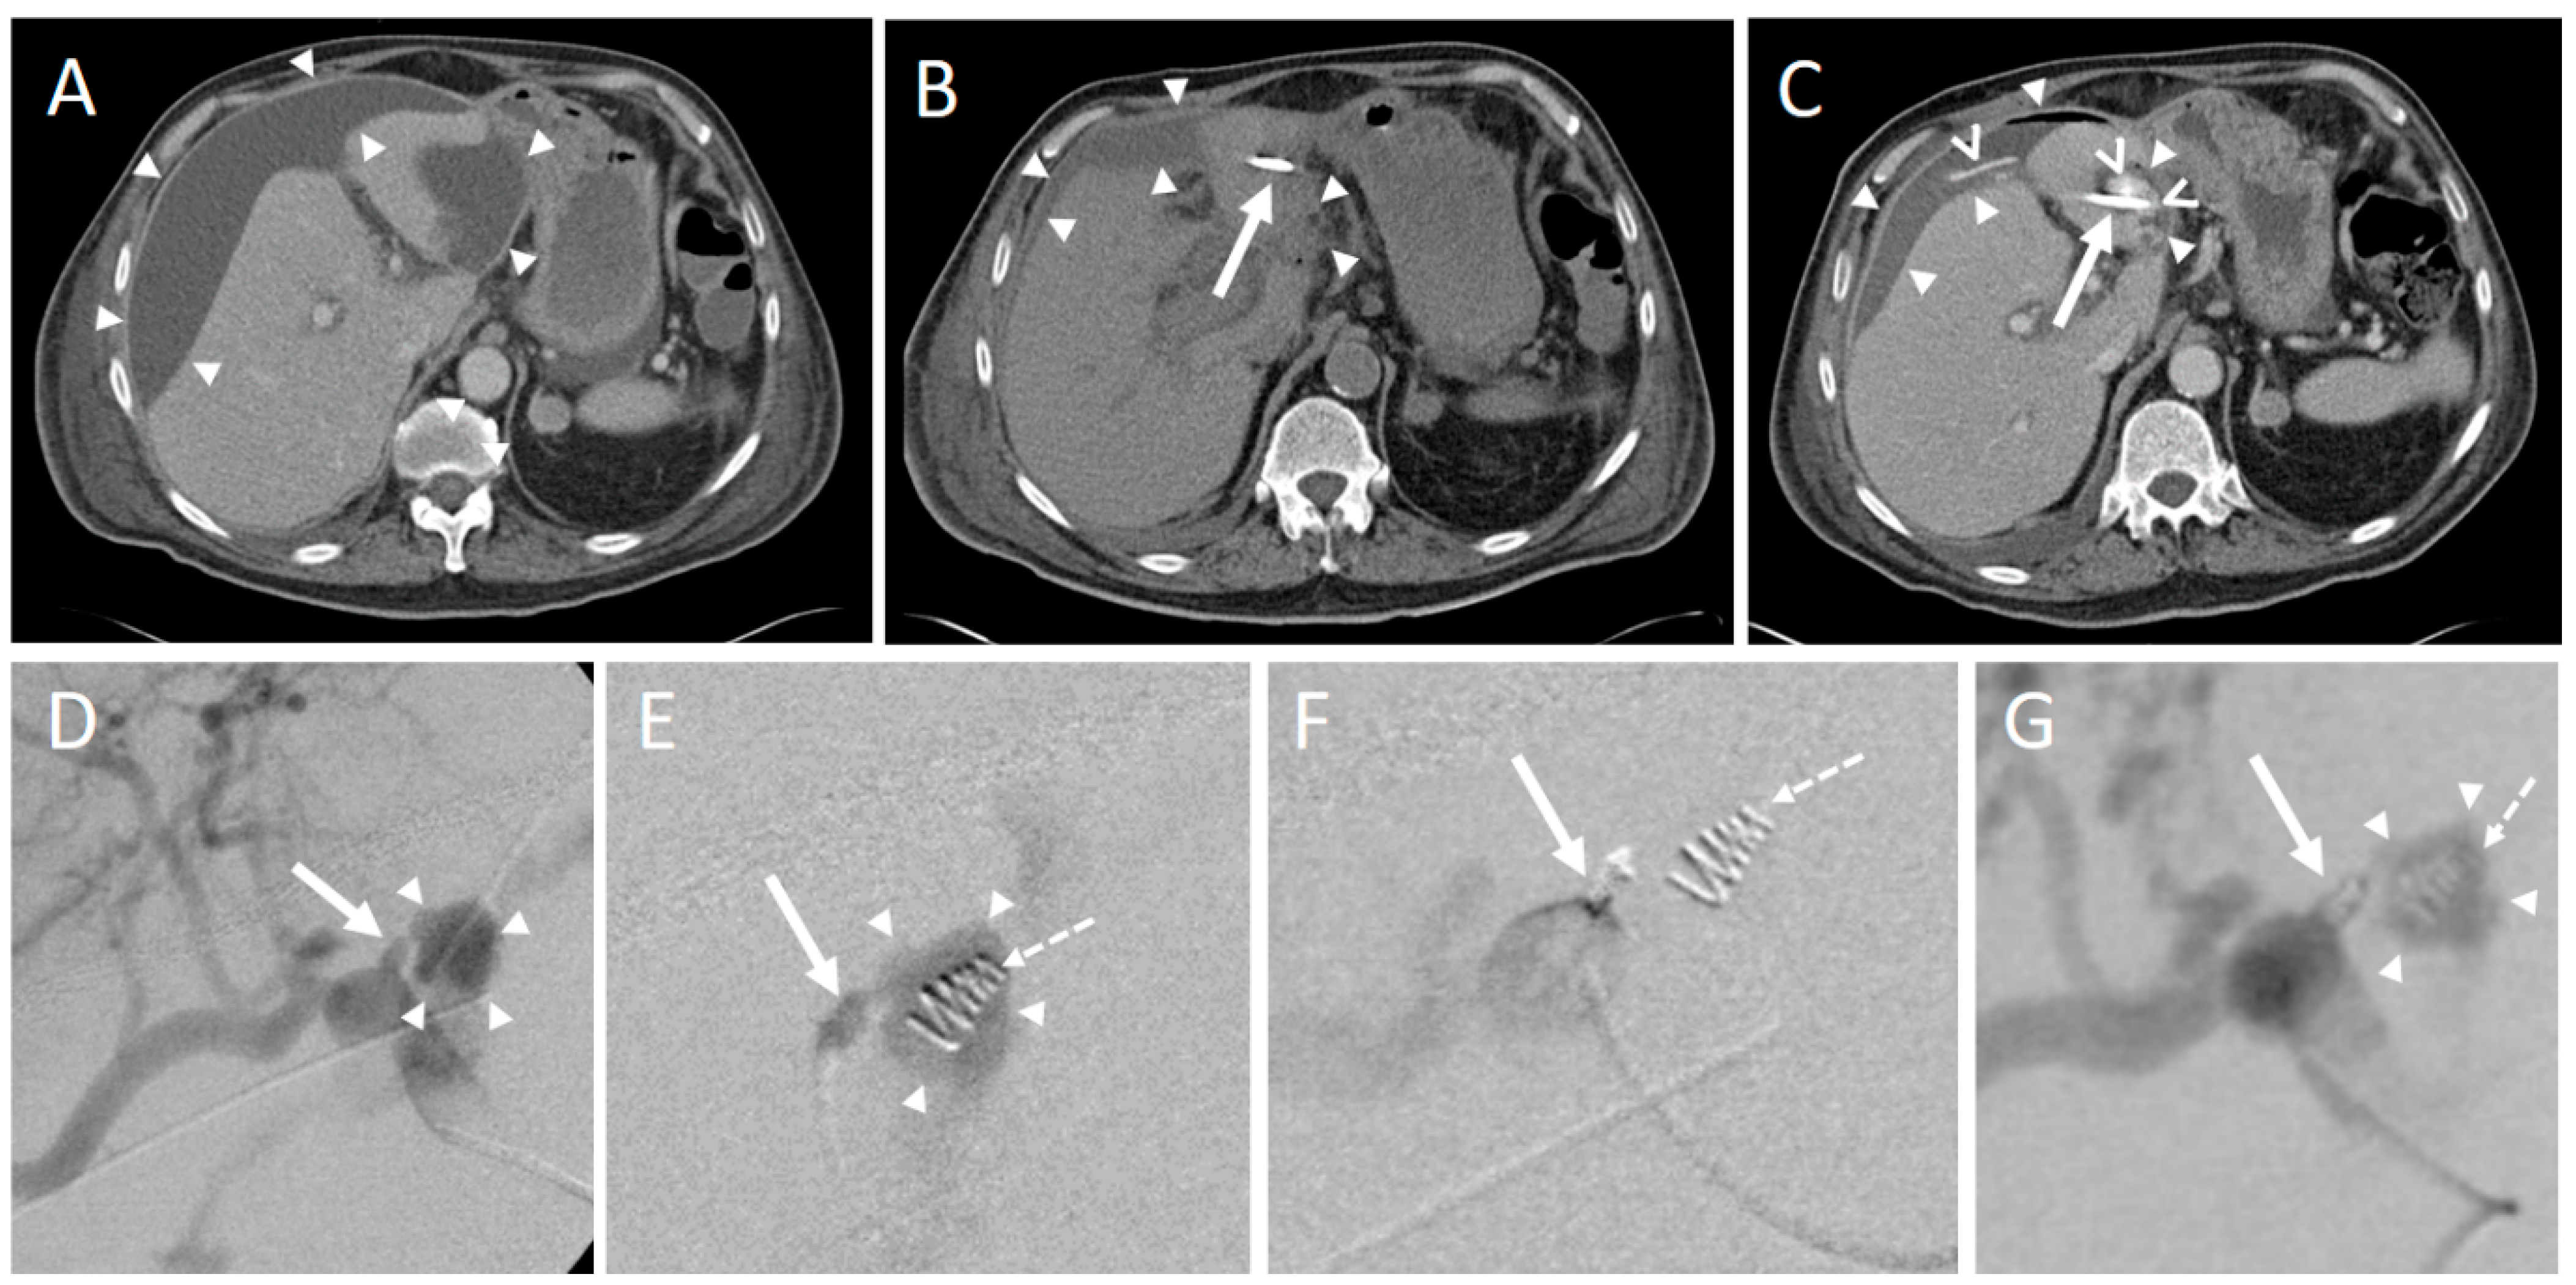

In one intervention, an instant replacement was necessary due to the dislocation of the initial drainage. In one case fluid collection was too small for drainage placement. Complications occurring during or immediately after the intervention were seen in three patients (1.8%). These comprised one major complication (according to SIR criteria) where operative revision was necessary (Table 4, Figure 3 and Figure 4).

Figure 3. An intervention with a minor complication according to SIR. (A) 70-year-old male developing jaundice. CT scan depicts a pancreatic head tumor (arrowheads) with infiltration of the hepatic artery and spread along the portal vein as well as the mesenteric root. (B) Infiltration and congestion of the pancreatic duct (dashed arrow), enlarged and roundly configured lymph node metastases (asterisk), and a previously endoscopically inserted drainage (arrows). Arrowheads: pancreatic head tumor. (C) An exploratory laparotomy including multiple biopsy samples of the pancreas was conducted. The Patient developed postoperative pancreatitis. Twenty-seven days after surgery a pancreatogenic, perisplenic subcapsular pseudocyst (star) was diagnosed on a CT scan. (D) Placement of an 8F drainage (arrow) within the fluid collection (arrowheads) in the right lateral decubitus position, guided by CT fluoroscopy. (E) Postinterventional unenhanced control CT scan shows the correct position of the drainage (arrow) and an almost complete disappearance of the fluid collection. (F) However, a small self-limiting pneumothorax (star) was observed in the lung window.

Figure 4. CT-guided drainage placement with a subsequent major complication according to SIR. (A) 71-year-old male underwent pancreaticoduodenectomy (PD) due to ductal pancreatic adenocarcinoma. Sixteen days later abdominal revision surgery with hematoma evacuation was performed due to arterial hemorrhage from the hepatic artery and small bowel segment resection due to adhesion ileus. Twenty-seven days after PD a perihepatic subcapsular fluid collection was diagnosed on a CT scan, mainly located at the ventrolateral and medial margins (arrowheads). (B) CT fluoroscopy-guided placement of a 10F Flexima® single lumen drainage (arrow; Boston Scientific, Marlborough, MA, USA) within the fluid collection (arrowheads). After placement, a significant reduction of the fluid was observed. (C) Contrast-enhanced CT control scan after eleven days revealed an increase of the subcapsular fluid collections mainly next to the right liver lobe (arrowheads). Contrast medium extravasation occurred inferior to the left liver lobe (segment 3) from the left gastric artery in terms of active bleeding from this vessel. Contrast medium extravasation could also be found in the fluid collection (open arrowheads). Arrow: drainage. An angiographic examination (not shown) performed immediately thereafter did not provide the source of the bleeding. (D) Repeated angiography after another 6 days showed extravasation of the contrast agent (arrowheads) from the left hepatic artery (arrow). (E) Superselective embolization of the bleeding was performed by placement of an 18/4 (Cook Medical, Bloomington, Indiana, USA) Tornado® microcoil in the vessel (arrow) supplying the hemorrhage. However, there was an initial misplacement of the coil (dashed arrow), which came to rest in the adjacent pseudoaneurysm (arrowheads). (F) Subsequently, placement of a second 18/4 Tornado® coil was conducted in the vessel neck (arrow; initially misplaced coil: dashed arrow). (G) The final angiographic control did not show a remaining contrast agent extravasation. Arrow: Vessel neck with coil; arrowheads: hematoma; dashed arrow: initially misplaced coil. In conjunction with the clinical course, the case was considered to be an arrosion hemorrhage induced by the drainage placement in combination with insufficiency of the biliodigestive anastomosis.